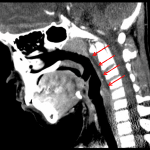

Indication: Neck swelling

- Retropharyngeal fluid collection without peripheral enhancement

- Enlarged adenoids

- Multiple enlarged bilateral cervical lymph nodes without suppuration

- Cervical lymphadenitis

- Retropharyngeal edema

Multiple enlarged bilateral cervical lymph nodes without suppurative changes. Associated retropharyngeal edema without discrete abscess.

Enlarged adenoid tonsillar tissue may indicate nasopharyngitis.